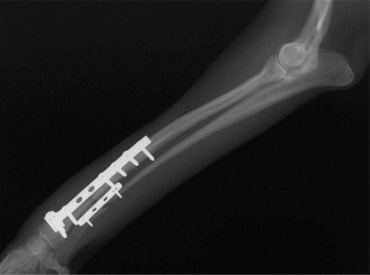

トイプードル 右遠位橈尺骨短斜骨折のALPSによる内固定

Locking Compression Plate

LCPは、スクリュー(ネジ)とプレート(金属の板)をロックする特殊な構造により骨折部位を固定する新しい世代のプレートシステムです。ひとつのホールでロッキングスクリューとスタンダードスクリューの使用を選択できるユニークな構造をしているため、骨折断端間の圧迫を目的とした従来型プレート固定法に加え、高い角度安定性を有するロッキングスクリューを用いた固定法の選択が可能です。従来のプレートシステムでは困難だった部分の骨折や癒合不全の症例に高い治療効果をもたらします。